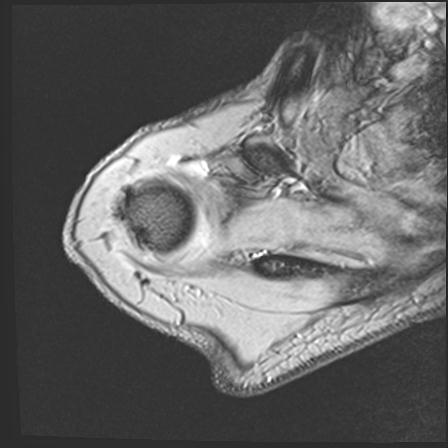

60058 3/9 11/4 右肩 2R+MRI 73歳男性 肩腱板損傷